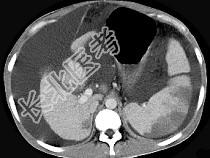

- 单项选择题患者男,29岁, 乙肝病史10余年,腹胀, 有移动性浊音,影像检查如图, 最全面的诊断是 ( )

A、肝硬化

B、肝硬化腹水

C、肝硬化腹水、脾梗、胆囊结石

D、大网膜膈下间位及脾梗

E、胆结石及脾梗